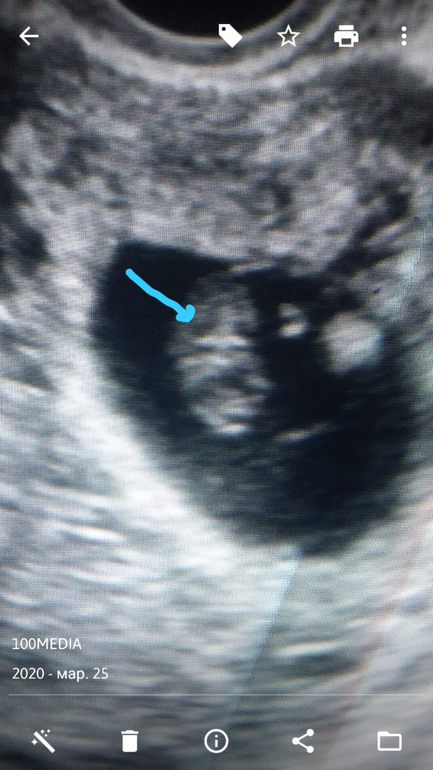

Беременность- 1 триместр ( только до 10 недель)Всего 14 мм, а уже видно место под глазки... Это такое чудо!!!!

Этому только 8 недель и то уже видно почти все 🙈🙈хотя понятно, чтт там еще и ручки и ножки по 2 мм 🙈а все равно, 1,5 см и уже человееек!